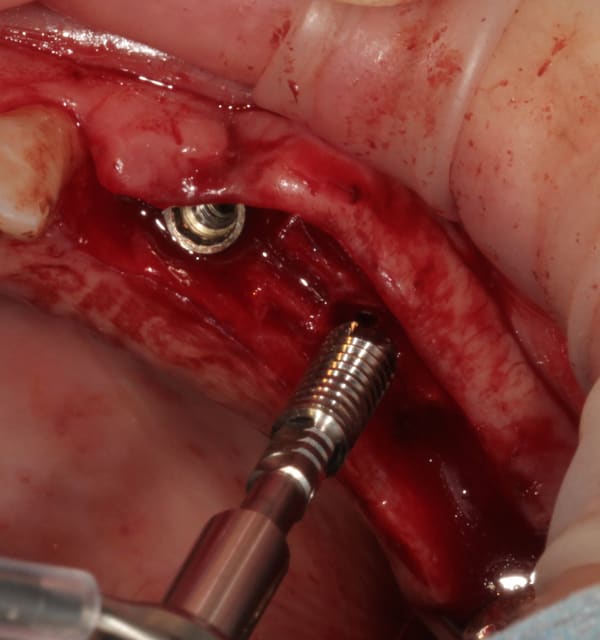

mise en place du conique lisse

L'outil de CLIO

contrôle, axe et profondeur

et un et deux et trois

D1 pour "assouplir"

éponge

implant lisse conique

éponge...